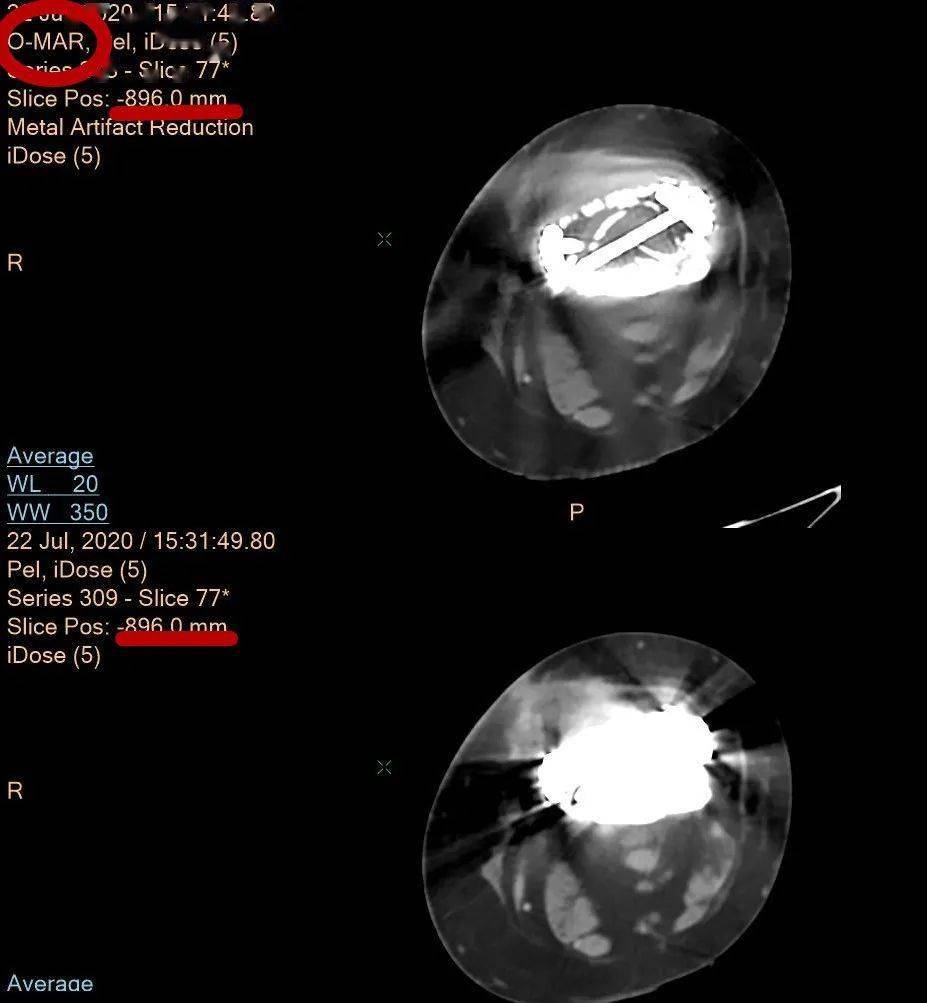

05 O-Mar去偽影平臺 展示金屬“隱身術”

有效去除金屬植入物偽影,清楚顯示金屬植入物周圍的組織結構信息,解決常規磁共振和CT都“頭疼”的歷史難題。

股骨髓內釘金屬偽影處理